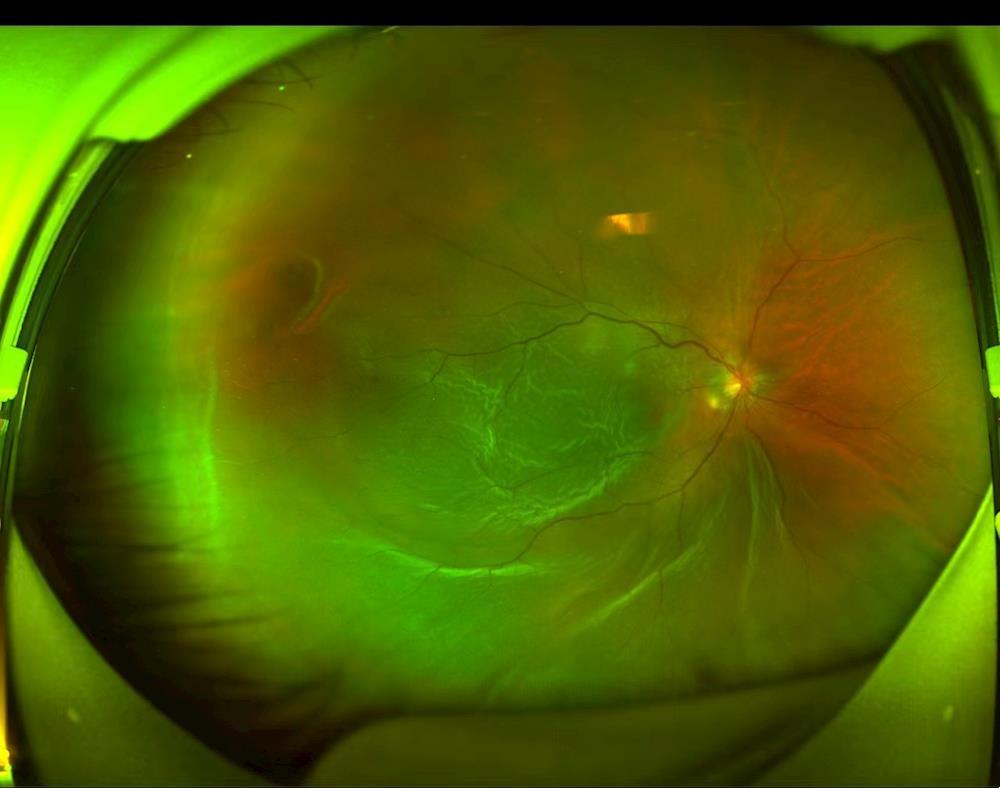

术前视网膜脱离

术后第一天视网膜平伏,激光斑明显